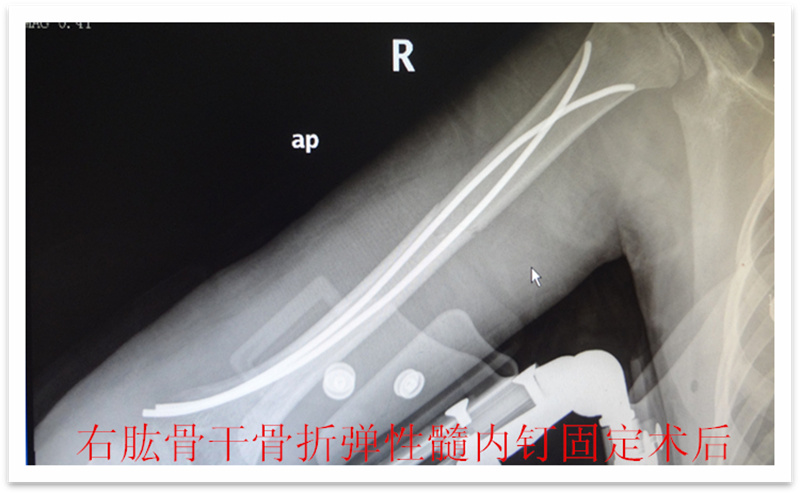

,弹性髓内钉内固定解决了这个矛盾。有人说,弹性髓内钉的出现是上天对儿童的恩惠。的确,弹性髓内钉是治疗小儿长管状骨骨骨折的一种理想、可靠的内固定方法。弹性髓内钉技术发源于法国,在欧洲广泛应用后,现已为全球所接受,被称为是儿童骨科界的一次革命。徐州儿童医院骨一科应用弹性髓内钉技术治疗四肢长管状骨骨折,具有创伤小、恢复快、并发症相对少,孩子能较快恢复正常生活、学习等优点。该技术先将骨折闭合复位,通过微小的切口将特制的弹性髓内钉置入骨髓腔,达到固定骨折的目的。适用于肱骨,股骨,尺桡骨等部位的常见骨折(图)。